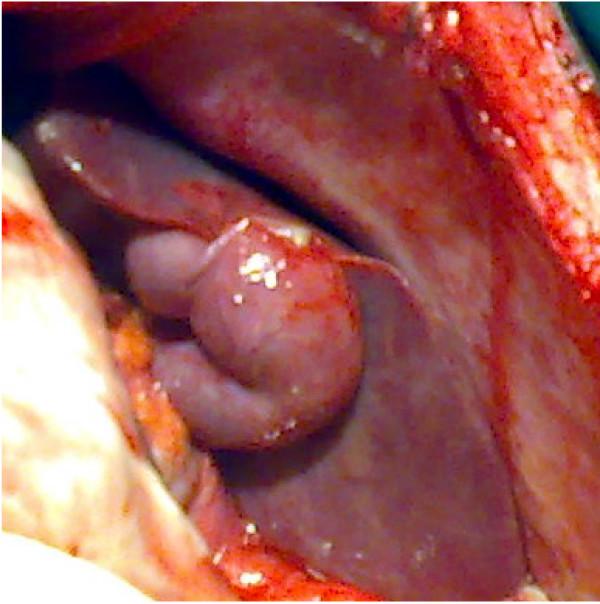

We report the case of a 20-year-old African man who presented to the emergency department with a 4-day history of diffuse abdominal pain, which began in his left iliac region and hypogastrium. After examination, we initiated a surgical exploration for peritonitis. We discovered a situs inversus at the left side of his liver, and his appendix was perforated in its middle third. A complementary post-operative thoracic and abdominal tomodensitometry revealed a situs inversus totalis.

我们报告一例20岁非洲男性病例,该患者因弥漫性腹痛4天就诊于急诊科,腹痛始于左髂区和下腹部。检查后,我们因腹膜炎进行了手术探查。我们发现其肝脏位于左侧,存在内脏反位,且阑尾在其中段三分之一处穿孔。术后补充的胸部和腹部体层摄影术显示为完全性内脏反位。